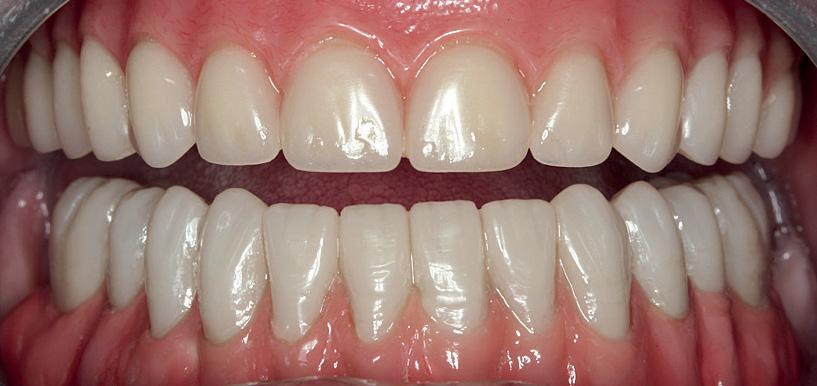

To achieve good primary closure, it was decided to modify the procedure and trim the roots up to the furcation to ensure a sound collar of alveolar bone and advance the buccal flap. This modification helped significantly during primary closure of the socket. LL8 tooth was removed completely as the roots became loose as well as UR8 and LU8. The post-operative phase was uneventful, and she recovered well (Fig 4).

This case also raises the limitation of the traditional method of imaging with an OPG and shows the importance of CBCT in deciding on the treatment plan. The patient initially visited her dentist in pain with the RL8 and the dentist attempted to remove the tooth to alleviate pain based only on her OPG finding which showed the root apex crossing the upper white line of IAC. Only after referring to a specialist, where CBCT revealed the course of IAC running between the roots of RL8, was the risk of nerve injury avoided.

question. Coronectomy offers a safe alternative where extraction of lower third molars has an established high risk of IAN injury. The evidence that is emerging so far is quite encouraging and in general shows good outcomes.